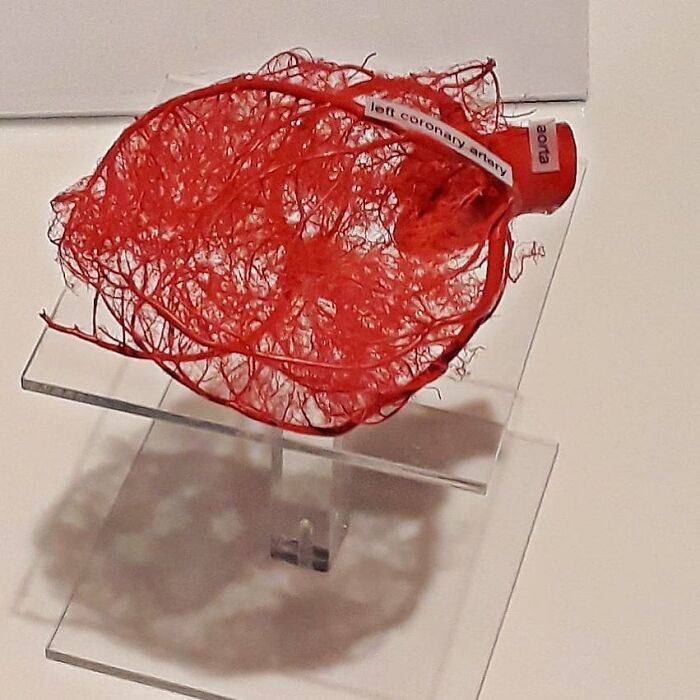

Heart Valve